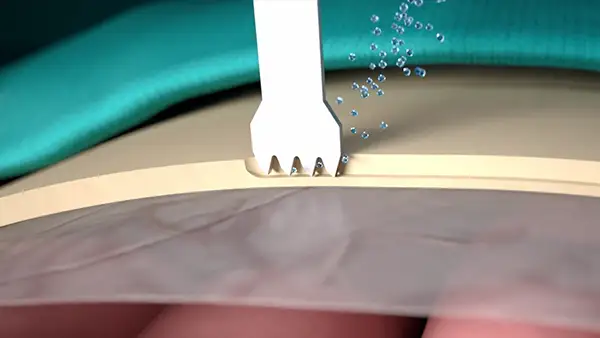

CAVITATION EFFECT

Maximum intra-operative visibility.

Blood-free surgical site.